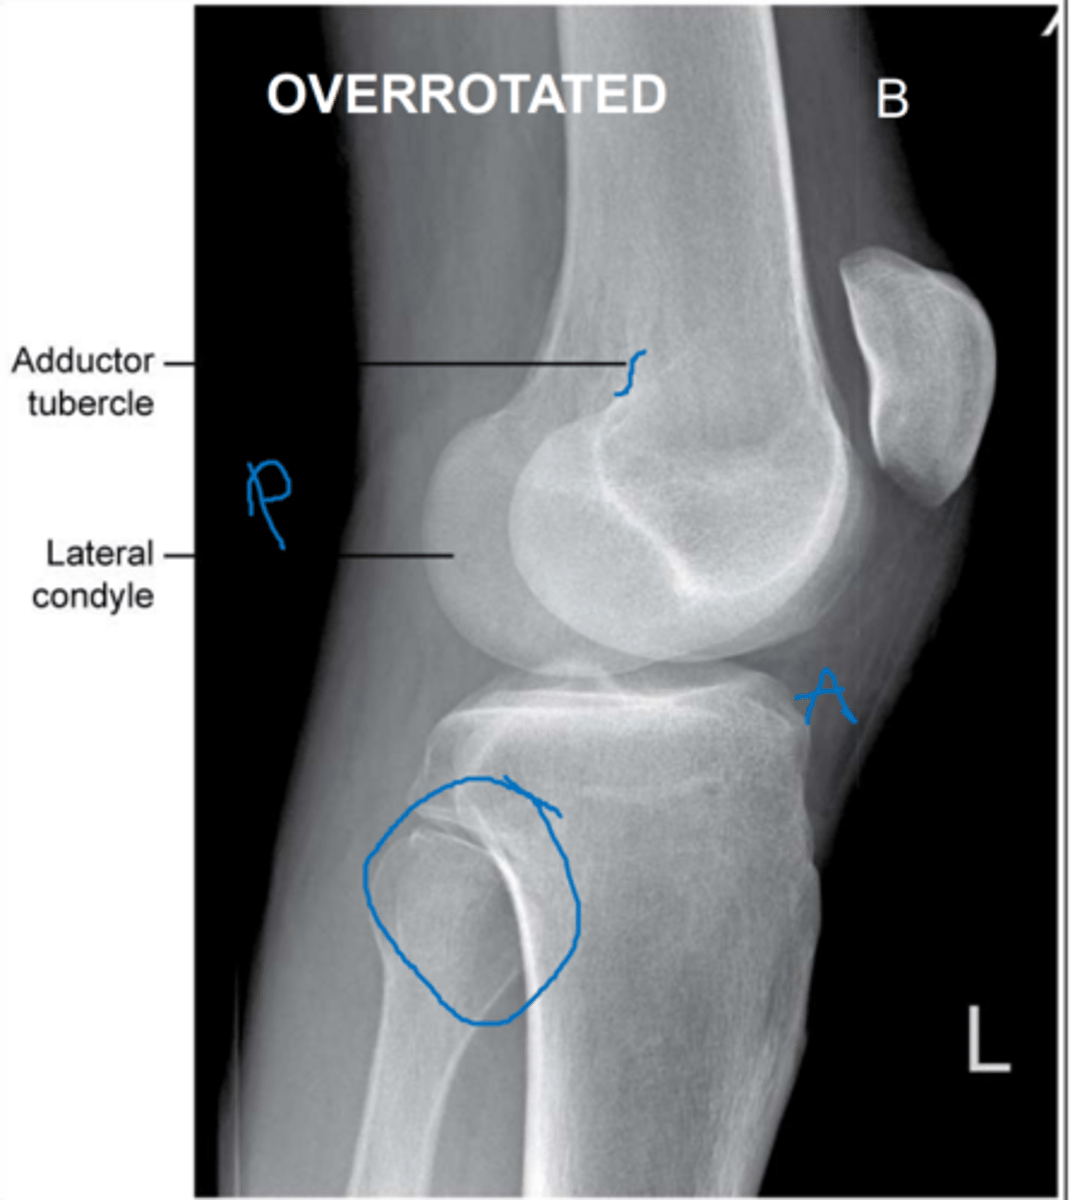

When doing a lateral knee projection, how can you tell if there is OVER-ROTATION?

- fibula is projected too POSTERIOR.

When doing a lateral knee projection, how can you tell if there is UNDER-ROTATION?

- fibula head is hidden behind the tibia